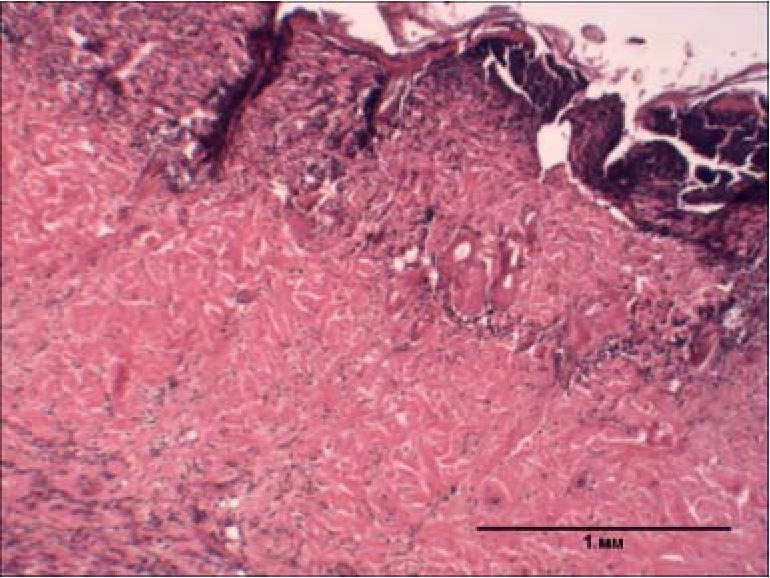

Рис. 3. Гистологическая картина кожи крысы через 8 суток после воздействия на неё воды температурой 90°С в течение 15 с (гематоксилин-эозин, ув. ×40)

На рисунке 3 видно, что эпидермис уплотнен с тенденцией к гомогенизации, клеточные слои не дифференцируются, ядра бледные, плохо контурированы, часть из них лизированы, роговые чешуйки на поверхности эпидермиса отсутствуют, на поверхности имеется отслаивающийся пласт гнойно-некротических масс (струп), подлежащая дерма под струпом с некрозом и густыми полиморфноядерными лейкоцитарными инфильтрациями, по периферии с формированием отграничивающего широкого лейкоцитарного вала. Отсутствие гибели животных в течение 30 суток на фоне глубокого ожога кожи на площади 10,8 ± 1,8% п. т. соответствовало термическому поражению легкой степени тяжести у крыс [3].